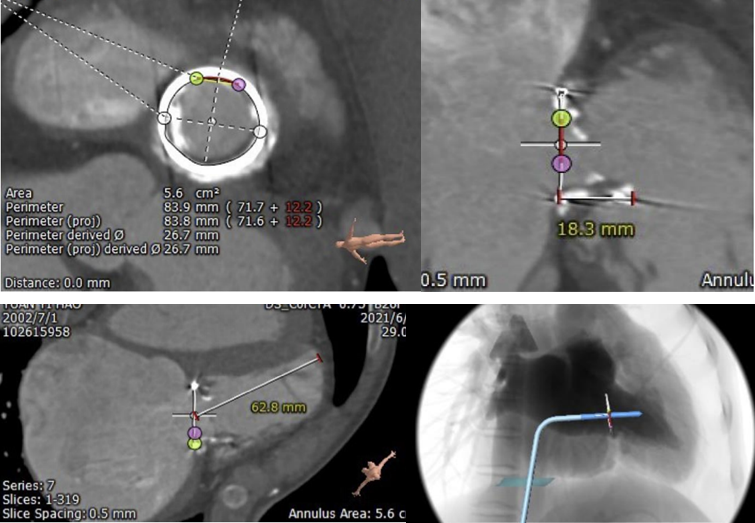

术前评估

术前计算机三维重建右心模型:

手术拟选择型号TAV 26 的Prizvalve®瓣膜进行瓣中瓣手术;设定充盈时直径达到26mm进行扩张;手术路径选择经股静脉入路。